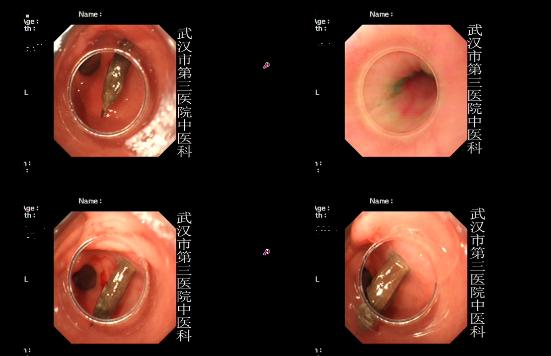

2.用X线检查,尤其是立位腹平片,通常可以发现膈下是否有游离气体。

3.用B超,CT检查等。